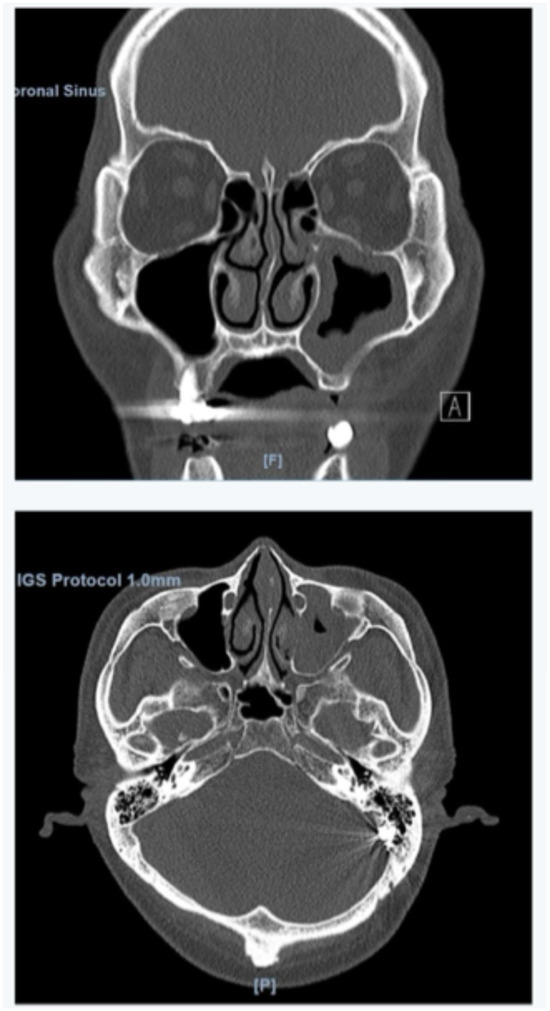

Development and Application of Nasal Spine-Guided Classification for Maxillary Sinus Pneumatization

Background/Objectives: The aim of this study was to develop a novel Nasal Spine-Guided Classification for assessing the alveolar vertical extension of the maxillary sinus and to evaluate its anatomical relationship with the roots of the posterior teeth using CBCT in a Saudi subpopulation. Methods: Maxillary sinus pneumatization was measured using cone-beam computed tomography for 380 patients. The assessment was performed along a horizontal plane extending between anterior and posterior nasal spine. In addition, pneumatization was evaluated in edentulous areas, and between the roots of multi-rooted teeth. Maxillary sinus membrane thickness was also measured. The results were expressed as mean, median and interquartile range, and considered statistically significant at a p-value < 0.05. Results: The mean maxillary sinus pneumatization on the left side was 8.8 ± 4.32 mm, and 8.58 ± 4.85 mm on the right side, with no statistically significant difference. The median of pneumatization in the edentulous area and between the roots on left side were 5.1 and 3.8 mm respectively, while on the right side, the median pneumatization was 5.03 and 3.04 mm. In addition, the proximity of the maxillary root apices to the sinus floor revealed a zero distance in 80.49% of the roots on the left side and in 79.48% on the right side. Furthermore, the results indicated no statistically significant association between maxillary sinus membrane thickness and pneumatization in the edentulous area. Conclusions: CBCT analysis revealed a predominance of advanced maxillary sinus pneumatization (Class III) and a high frequency of direct contact between posterior maxillary root apices and the sinus floor in the studied population. Additionally, no significant association was identified between maxillary sinus membrane thickness and sinus pneumatization in edentulous areas. Full article

Show Figures

Figure 1